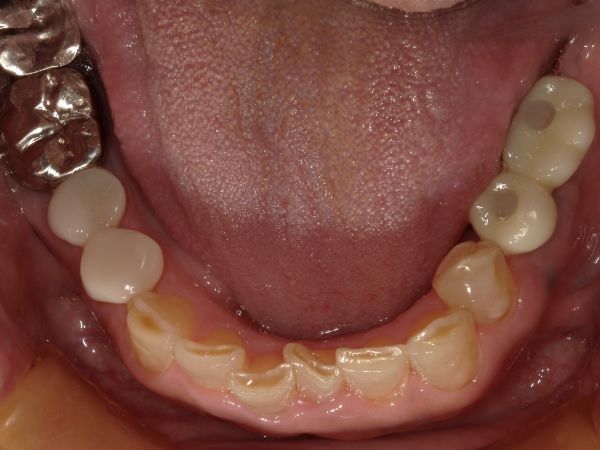

ジルコニアクラウンが完成しましたので、微調整を行い、セットしました。こちらがセット後の写真とレントゲン写真になります。

今回は、インプラントにトラブルがあった際にすぐに対応できるように、ネジで固定するタイプでセットを行いました。

ネジで固定するタイプは被せ物を外したい際に、容易に被せ物を外すことができます。また、インプラント周囲炎(インプラントの歯周病)の原因となるセメントの取り残しもございません。